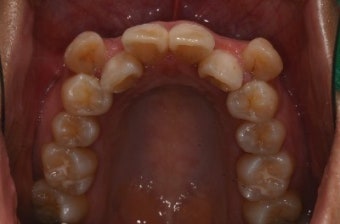

- 자연 치아 vs 임플란트: 자연 치아는 완충 역할을 하는 치주 인대가 있으나, 임플란트는 없어 합병증 발생 위험↑.

- 합병증(나사 풀림, 파절 등)은 초기 자각 어려움 → 정기 검진 필수.